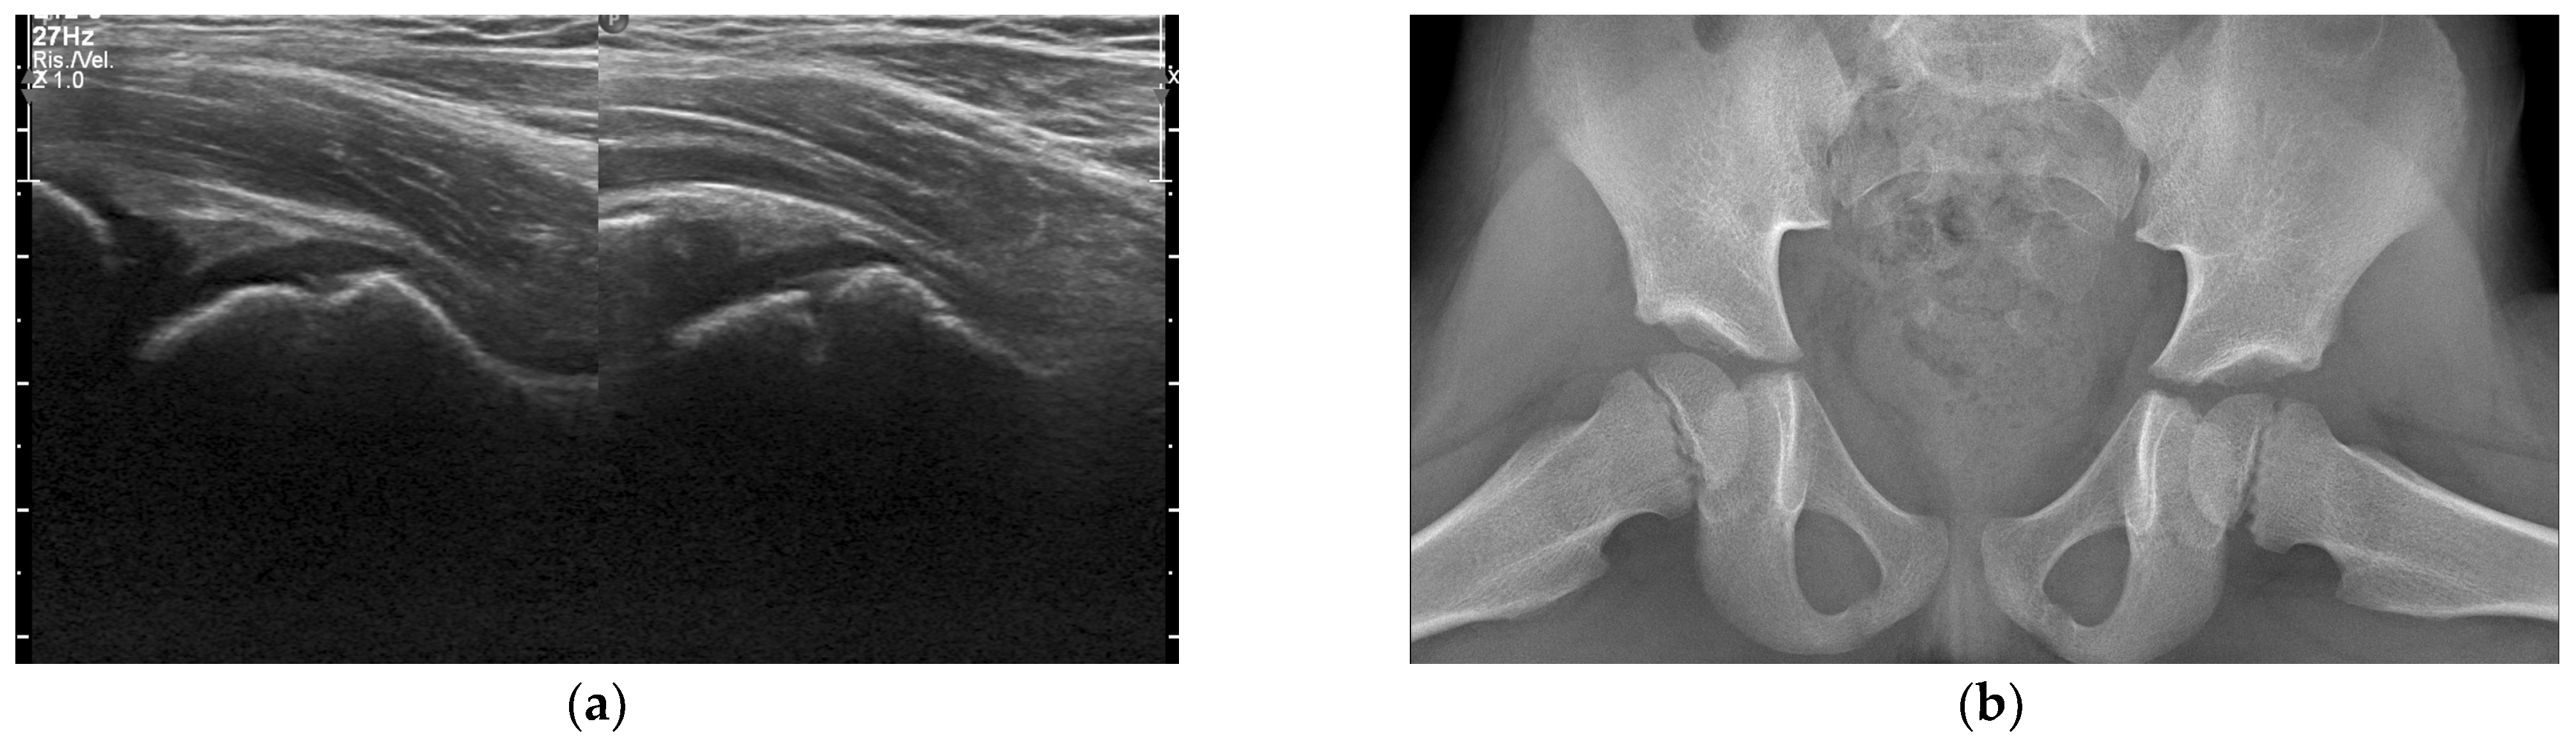

3.3. Radiologic Investigations

- Trusen, A.; Beissert, M.; Schultz, G.; Chittka, B.; Darge, K. Ultrasound and MRI features of pyomyositis in children. Eur. Radiol. 2003, 13, 1050–1055. [Google Scholar] [CrossRef]

- Peetrons, P. Ultrasound of muscles. Eur. Radiol. 2002, 12, 35–43. [Google Scholar] [CrossRef]